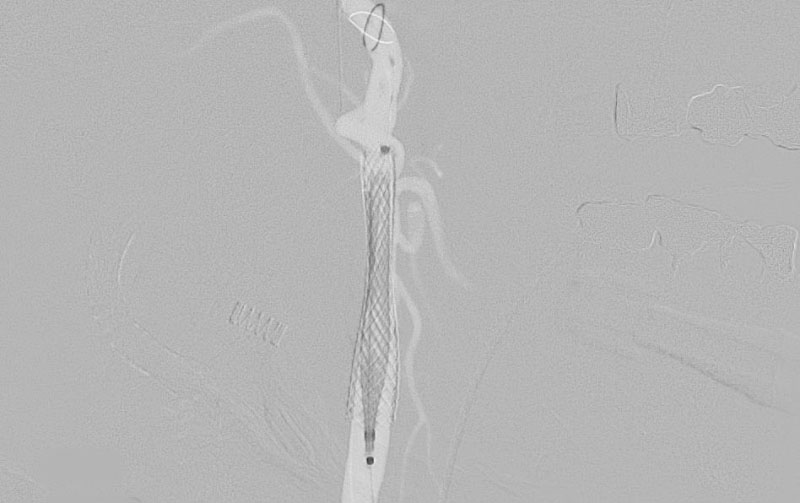

症例 '22年6月

No.

1239

手術日

病名

年齢

紹介元

備考

'22年6月18日

右内頚動脈狭窄症

80代

院内外来

手術写真

治療

前

中

後